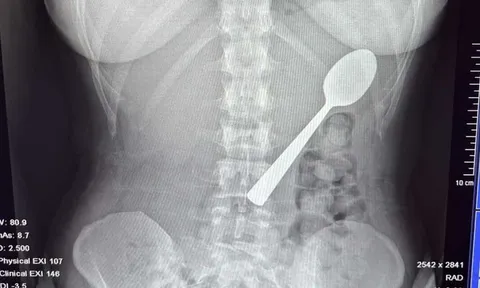

Bé trai 13 tuổi chảy máu nhiều, bác sĩ sốc khi phát hiện bí mật "đáng sợ" ở cổ - Ảnh 3.Đau quặn bụng dữ dội, người phụ nữ 55 tuổi phát hiện bí mật đáng sợĐỌC NGAY